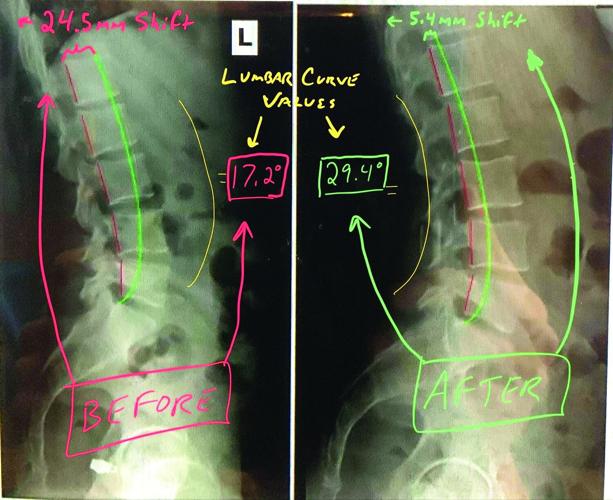

kAmp A@DEFC6 >:D>2E49 :? 9@H >F49 4FCG6 2 A6CD@? 92D :? E96:C =@H6C 324<] wJA@=@C5@D:D WE@@ =:EE=6 4FCG6 @C DEC2:89E 324< DJ?5C@>6X @C 9JA6C=@C5@D:D WE@@ >F49 4FCG6 @C DH2J324< DJ?5C@>6X 42? 42FD6 D:8?:7:42?E AC@3=6>D WA2:?[ 5686?6C2E:@?X :? E96 =@H6C 324<]k^Am

kAmp 962=E9J 2>@F?E @7 =@H6C 324< 4FCG6 :D G:E2==J :>A@CE2?E 3642FD6 :E 2==@HD 7@C D9@4< 23D@CAE:@? W=:<6 2 DAC:?8X H96? J@F H2=<[ CF?[ D:E[ =:7E … 6E4] %@@ >F49 @C E@@ =:EE=6 =F>32C 4FCG6 :?4C62D6D 3:?5:?8 AC6DDFC6 @? E96 7246E ;@:?ED @C :?4C62D6D D9@4< @? E96 5:D4D 2?5 3@E9 6BF2E6 E@ >@C6 7@C46 @? E96 =@H6C 324< ;@:?ED[ H9:49 6BF2E6D E@ >@C6 H62C 2?5 E62C 2?5 >@C6 A2:? @G6C E:>6]k^Am

kAmrFCC6?E C6D62C49 ?@H 56>@?DEC2E6D E92E 5F6 E@ G2C:2E:@?D :? 6249 A6CD@?’D A6=G:4 >@CA9@=@8J W3@?6 7@C>2E:@?X[ E96C6 :D 2? :562= W=62DE DEC6DD7F=X A@D:E:@? 7@C E96:C =@H6C 324< E@ H@C< 36DE] %9:D AC65:4E:G6 G2=F6 42? 36 :56?E:7:65 H:E9 DA64:7:4 )\C2JD]k^Am

kAmwJA@^9JA6C =@C5@D:D 4@CC64E:@? C6=:6D @? AC@A6C :56?E:7:42E:@?]k^Am

kAmx? @C56C E@ 244FC2E6=J 2DD6DD =F>32C =@C5@D:D )\C2JD >FDE 36 A2CE @7 E96 5:28?@DE:4 A:4EFC6] tG6? 2 962=E9\42C6 AC@G:56C EC2:?65 :? A@DEFC6 2?5 3:@DECF4EFC2= 2DD6DD>6?E D@>6E:>6D >:DD6D E9:D 6IE6C?2==J]k^Am

kAmq642FD6 @7 E96 :?4C65:3=6 4@>A6?D2E:?8 ?2EFC6 @7 @FC 3@5:6D[ E96J @7E6? 9:56 H92E :D 92AA6?:?8 @? E96 :?D:56] tG6? :7 E96 49:C@AC24E@C @C E96C2A:DE 42? D66 2 9JA@=@C5@D:D 6IE6C?2==J[ E96J H:== ?@E 36 23=6 E@ >62DFC6 E96 >28?:EF56 @C 244FC2E6=J 4@>6 FA H:E9 2 D276 EC62E>6?E A=2? E@ 4@CC64E :E H:E9@FE )\C2JD]k^Am